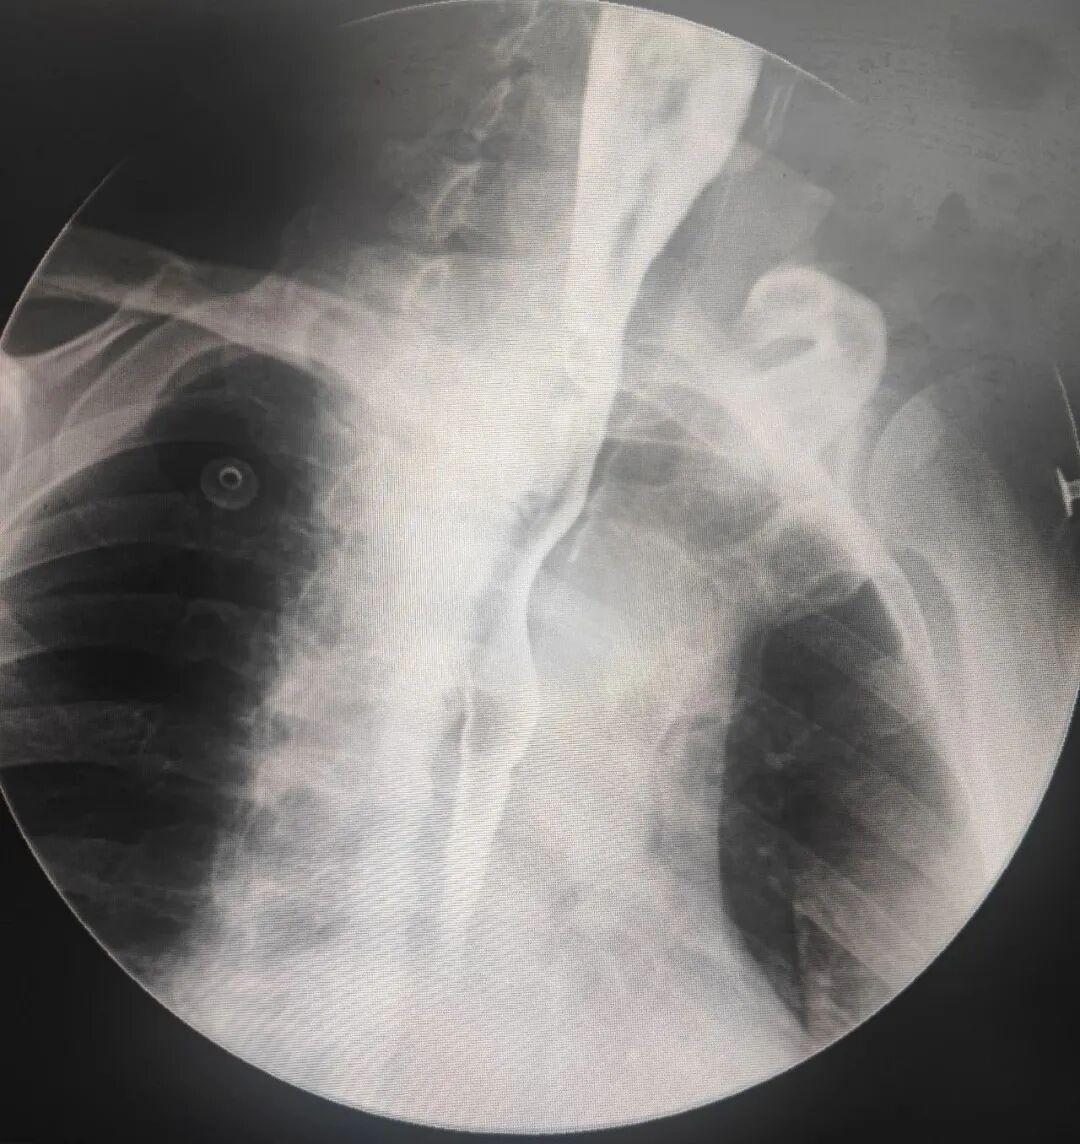

术后第二天行上消化道造影提示瘘口完全被夹闭。